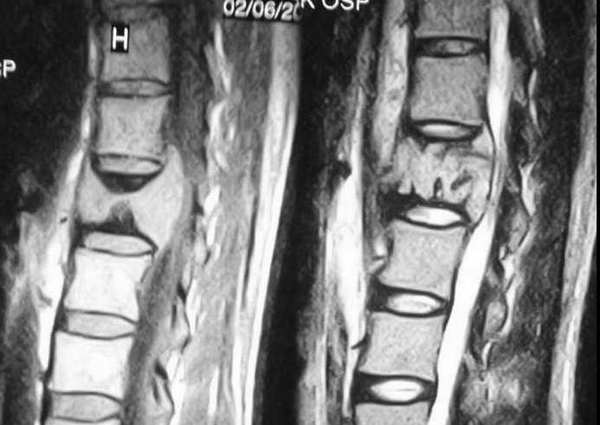

男,42岁。半年前体检发现右侧肺门肿大,mri示右侧肺门淋巴结肿大。腰背部疼痛伴右腿麻木1月入院。腹部b超示肝、胆、胰腺、脾、肾、前列腺及膀胱未见异常。afp、cea、ca199均正常。

增强图像显示不清,好像有肺门及纵隔与腋下淋巴结肿大,右侧胸腔积液,腰1椎体骨质破坏,椎旁软组织肿块形成,其后硬脊膜囊明显受压。考虑淋巴瘤可能。其他待排。

腰椎骨质破坏,但未侵及椎间盘,椎前软组织肿胀,考虑腰椎转移瘤可能

腰椎骨质破坏,但未侵及椎间盘考虑腰椎转移瘤可能